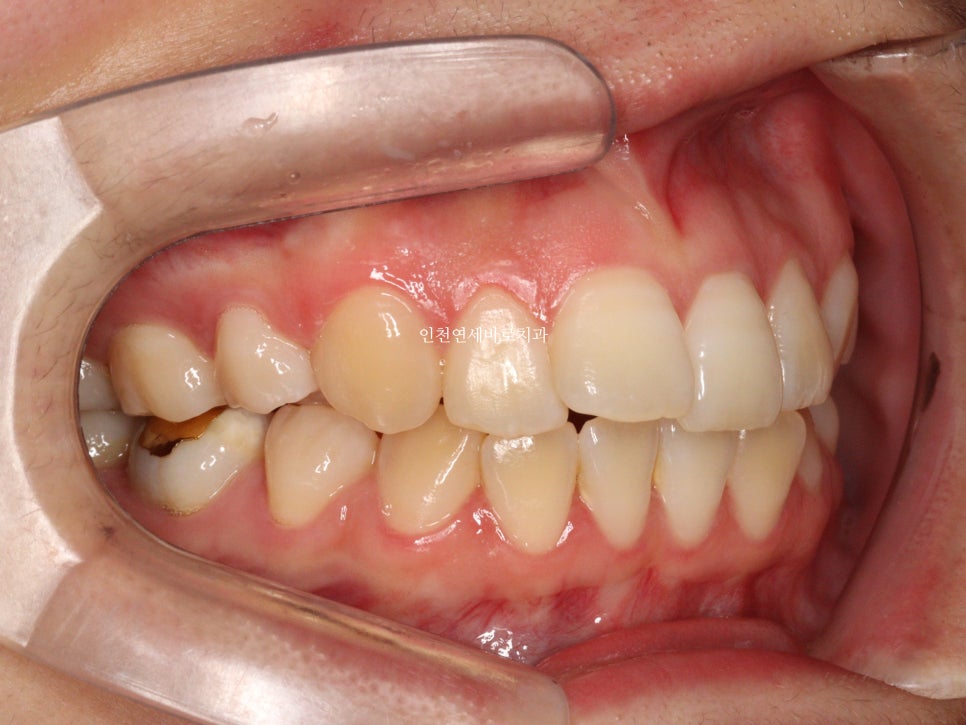

약 3개월의 변화모습입니다.

그리고 치료가 마무리 된 후의 모습입니다.

하지만 인비절라인은 전체교정에 준하는

치아와 주변조직에 무리가 되지 않는 범위에서의 확장을 만들어낼 수 있어

앞니의 뻗침을 최소화 할 수 있는 장점이 있습니다.

위 환자분의 재교정 치료기간은 약 7개월입니다.

7개월동안 병원은 두번 왔구요.